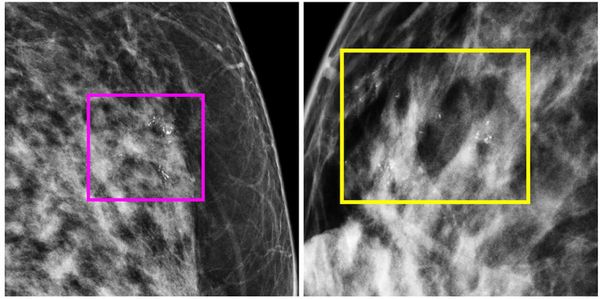

The use of radiomics for mammography may help predict the development of occult invasive cancer in women with ductal carcinoma in situ (DCIS), according to a new study.